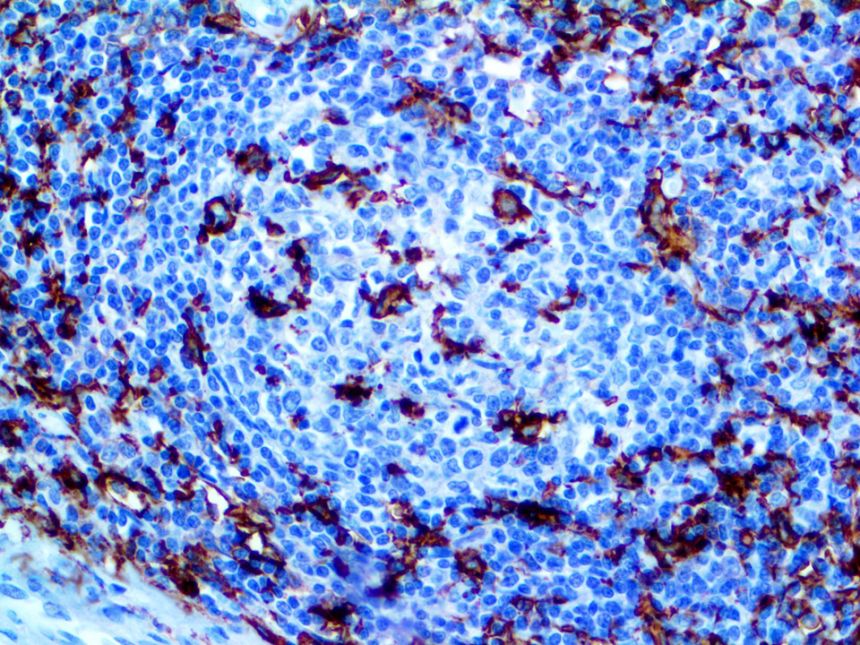

It is the ICU physician who is most likely to witness one of the deadliest manifestations of the abnormal immunological response, the cytokine storm syndrome (CSS). This response is also referred to by some as the cytokine release syndrome (CRS). CSS is characterized by continuous activation and expansion of macrophage and lymphocyte populations, which secrete large amounts of cytokines, causing the cytokine storm. This massive cytokine release is akin to hemophagocytic lymphohistiocytosis (HLH) disease, a syndrome characterized by initial unchecked and persistent activation of cytotoxic T lymphocytes and NK cells.

Clinical and laboratory manifestations of HLH include fever, enlarged liver and/or spleen, neurologic dysfunction, coagulopathy, liver dysfunction, cytopenias (i.e., low levels of erythrocytes, leukocytes, and/or platelets), hypertriglyceridemia, hyperferritinemia, hemophagocytosis, and eventually diminished NK cell activity as the immune system becomes progressively paralyzed. HLH can be familial (primary HLH) or secondary to another disease process (sHLH), such as rheumatic disease, in which it is referred to as macrophage activation syndrome (MAS, characterized by elevated ferritin).